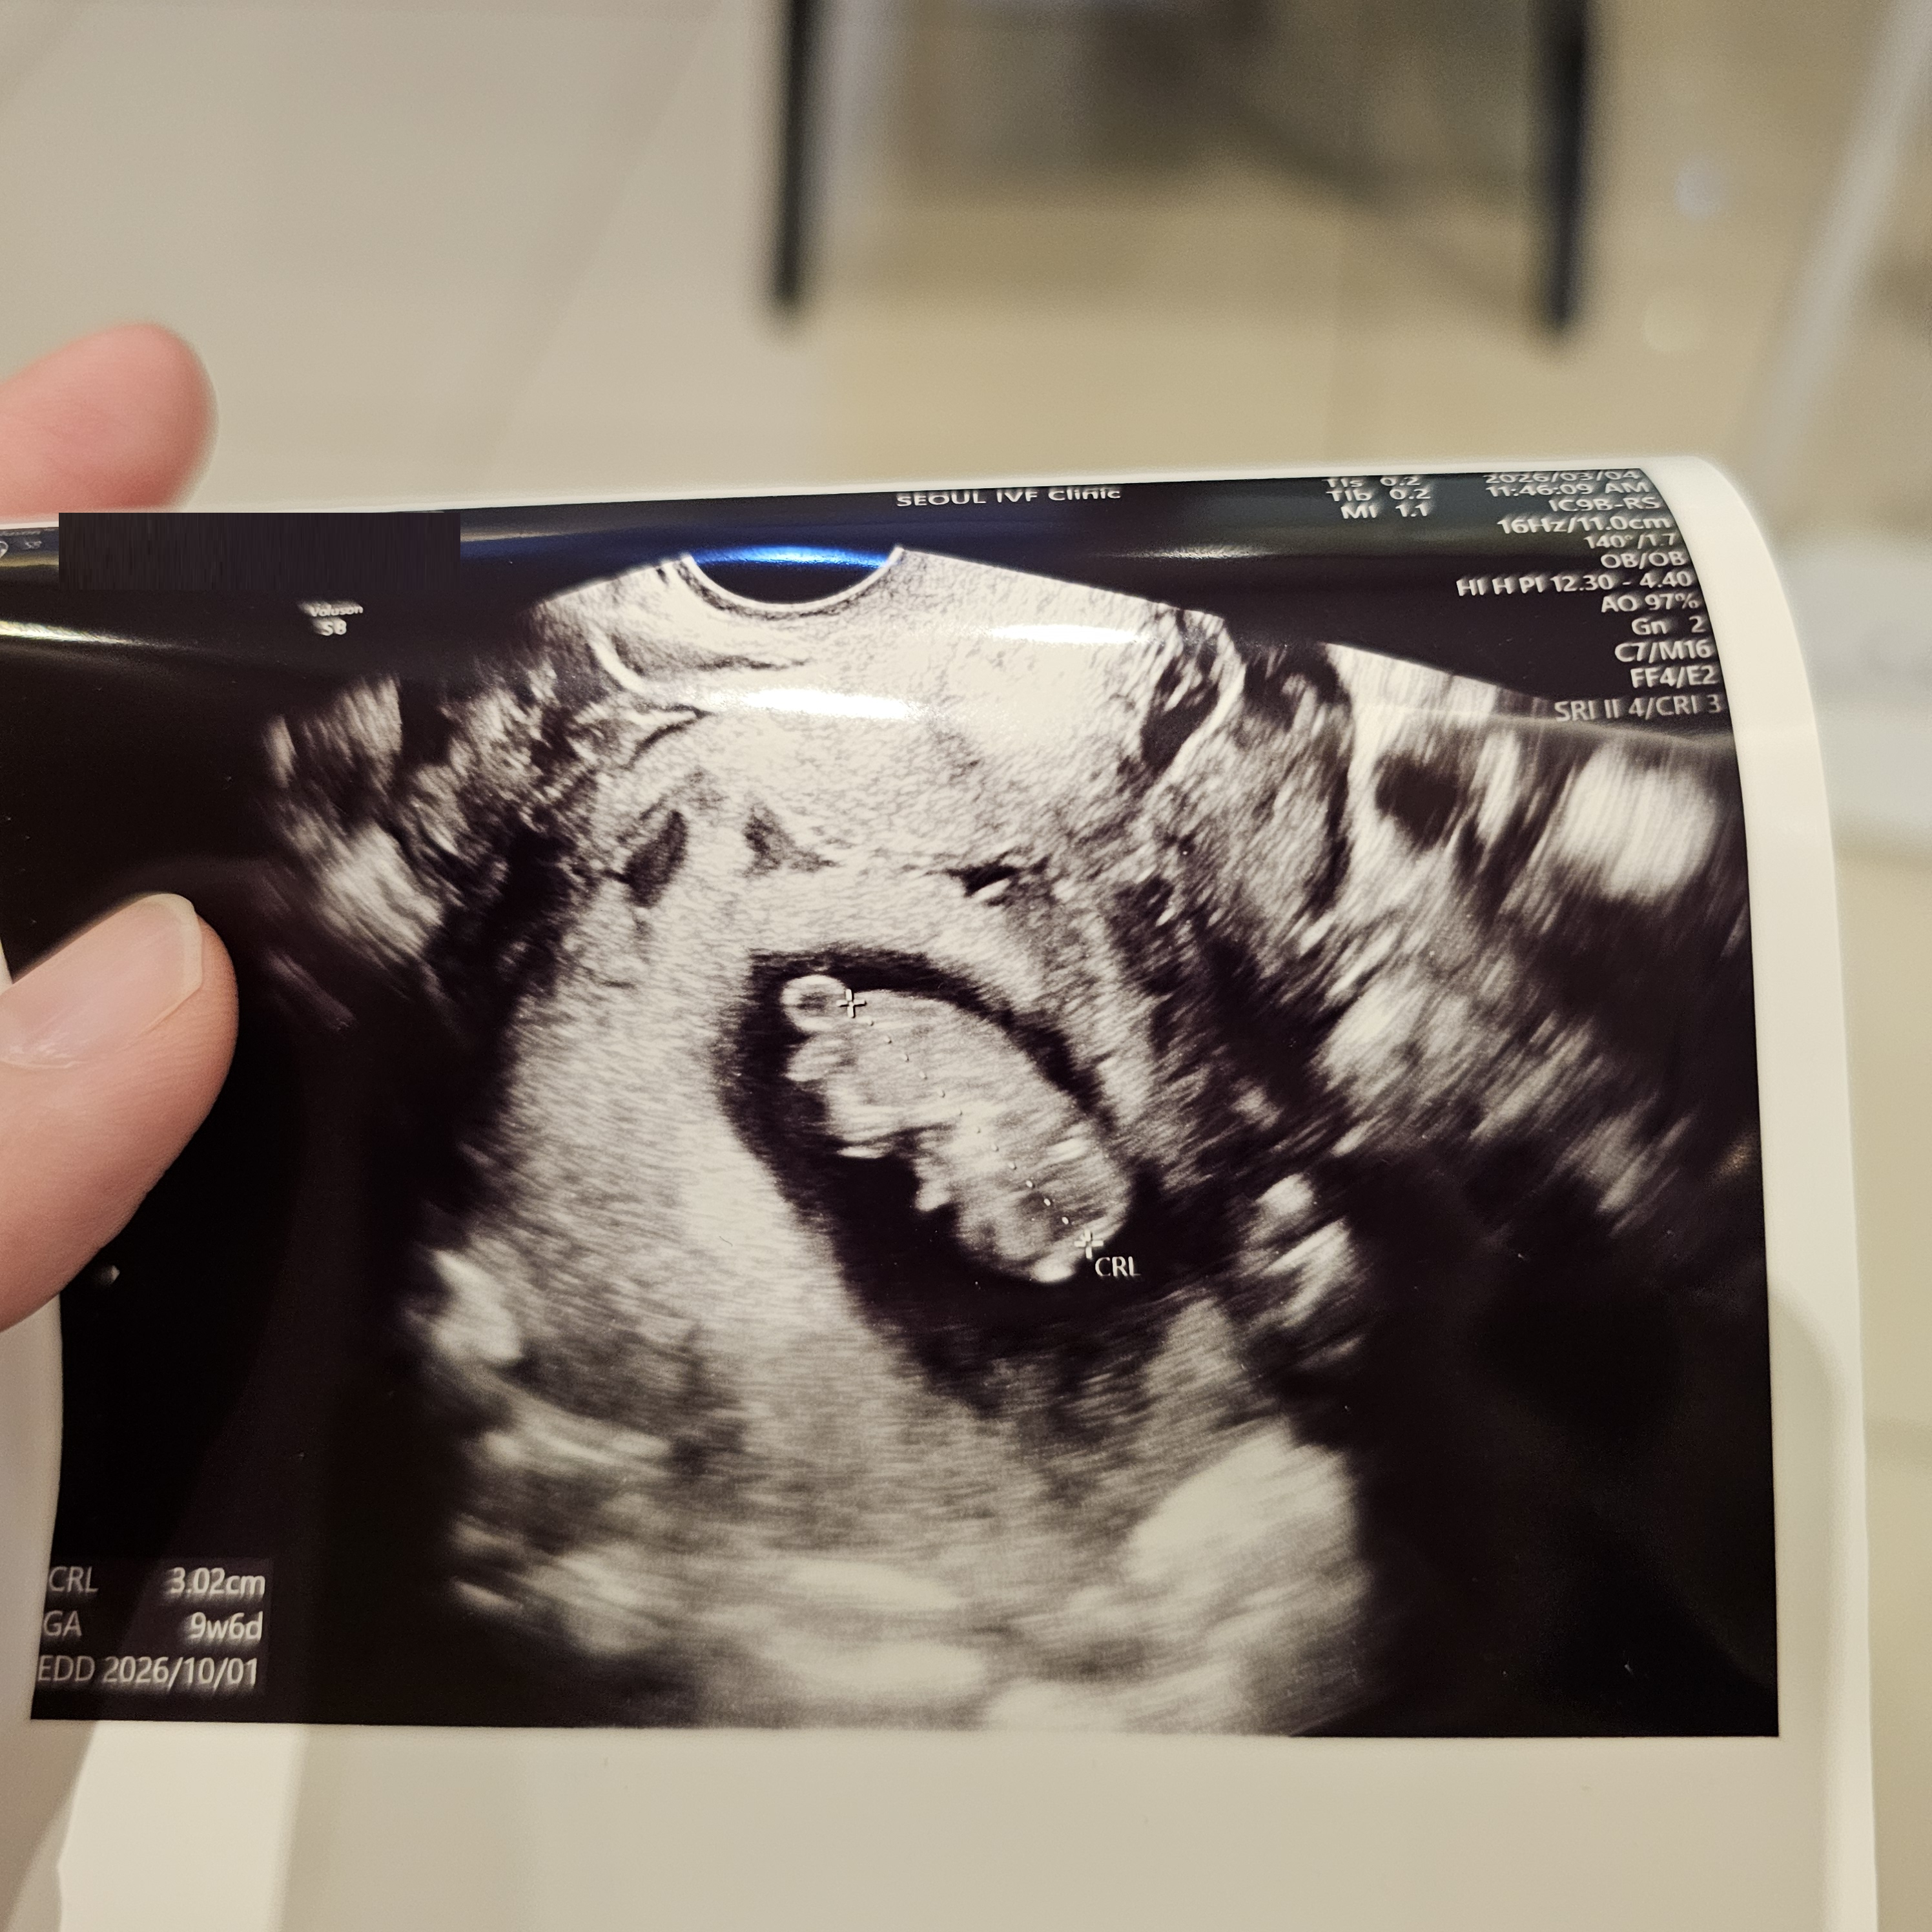

| 가슴 떨리는 임신 이야기를 공유해 주세요. | 임신이 되지 않아 서울아이비에프여성의원을 찾게 되었고, 과배란 → 인공수정 → 시험관 시술 과정을 거쳐 임신에 성공했습니다. 중간에 자궁내시경도 함께 진행했습니다. 피검사 당일 임신테스트기로 두 줄을 확인했을 때, ‘나도 임신이 되는 몸이구나’라는 생각에 벅찬 감정을 느꼈습니다. 비록 초기 수치는 높지 않았지만, 2차 피검에서 수치가 잘 상승(더블링)하고 아기집 확인을 위해 내원하라는 이야기를 들었을 때 이번에는 정말 되겠다는 확신이 들었습니다. 함께 기뻐해주신 이유정 원장께 늘 감사한 마음입니다. |

| 치료 도중 느꼈던 가장 기뻤던 순간과 절망적인 것들은 무엇인가요? 잊지 못할 경험이 있나요? | 가장 기뻤던 순간은 아기집을 확인하고, 난황까지 본 뒤 2주 후 심장 소리를 들었을 때였습니다. 그 모든 과정이 하나하나 기적처럼 느껴졌습니다. 가장 절망적이었던 순간은 상태가 가장 좋았던 배아를 이식했음에도 실패했을 때였습니다. |